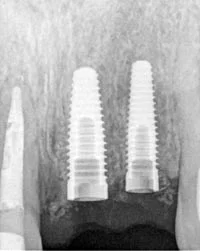

A dental implant is a small prosthetic post that is placed into the bone of the upper or lower jaw. The post functions as the root portion of the lost natural tooth and serves as an anchor for replacement tooth. Once the post has settled an artificial tooth is attached to fill the space that was once your missing tooth.